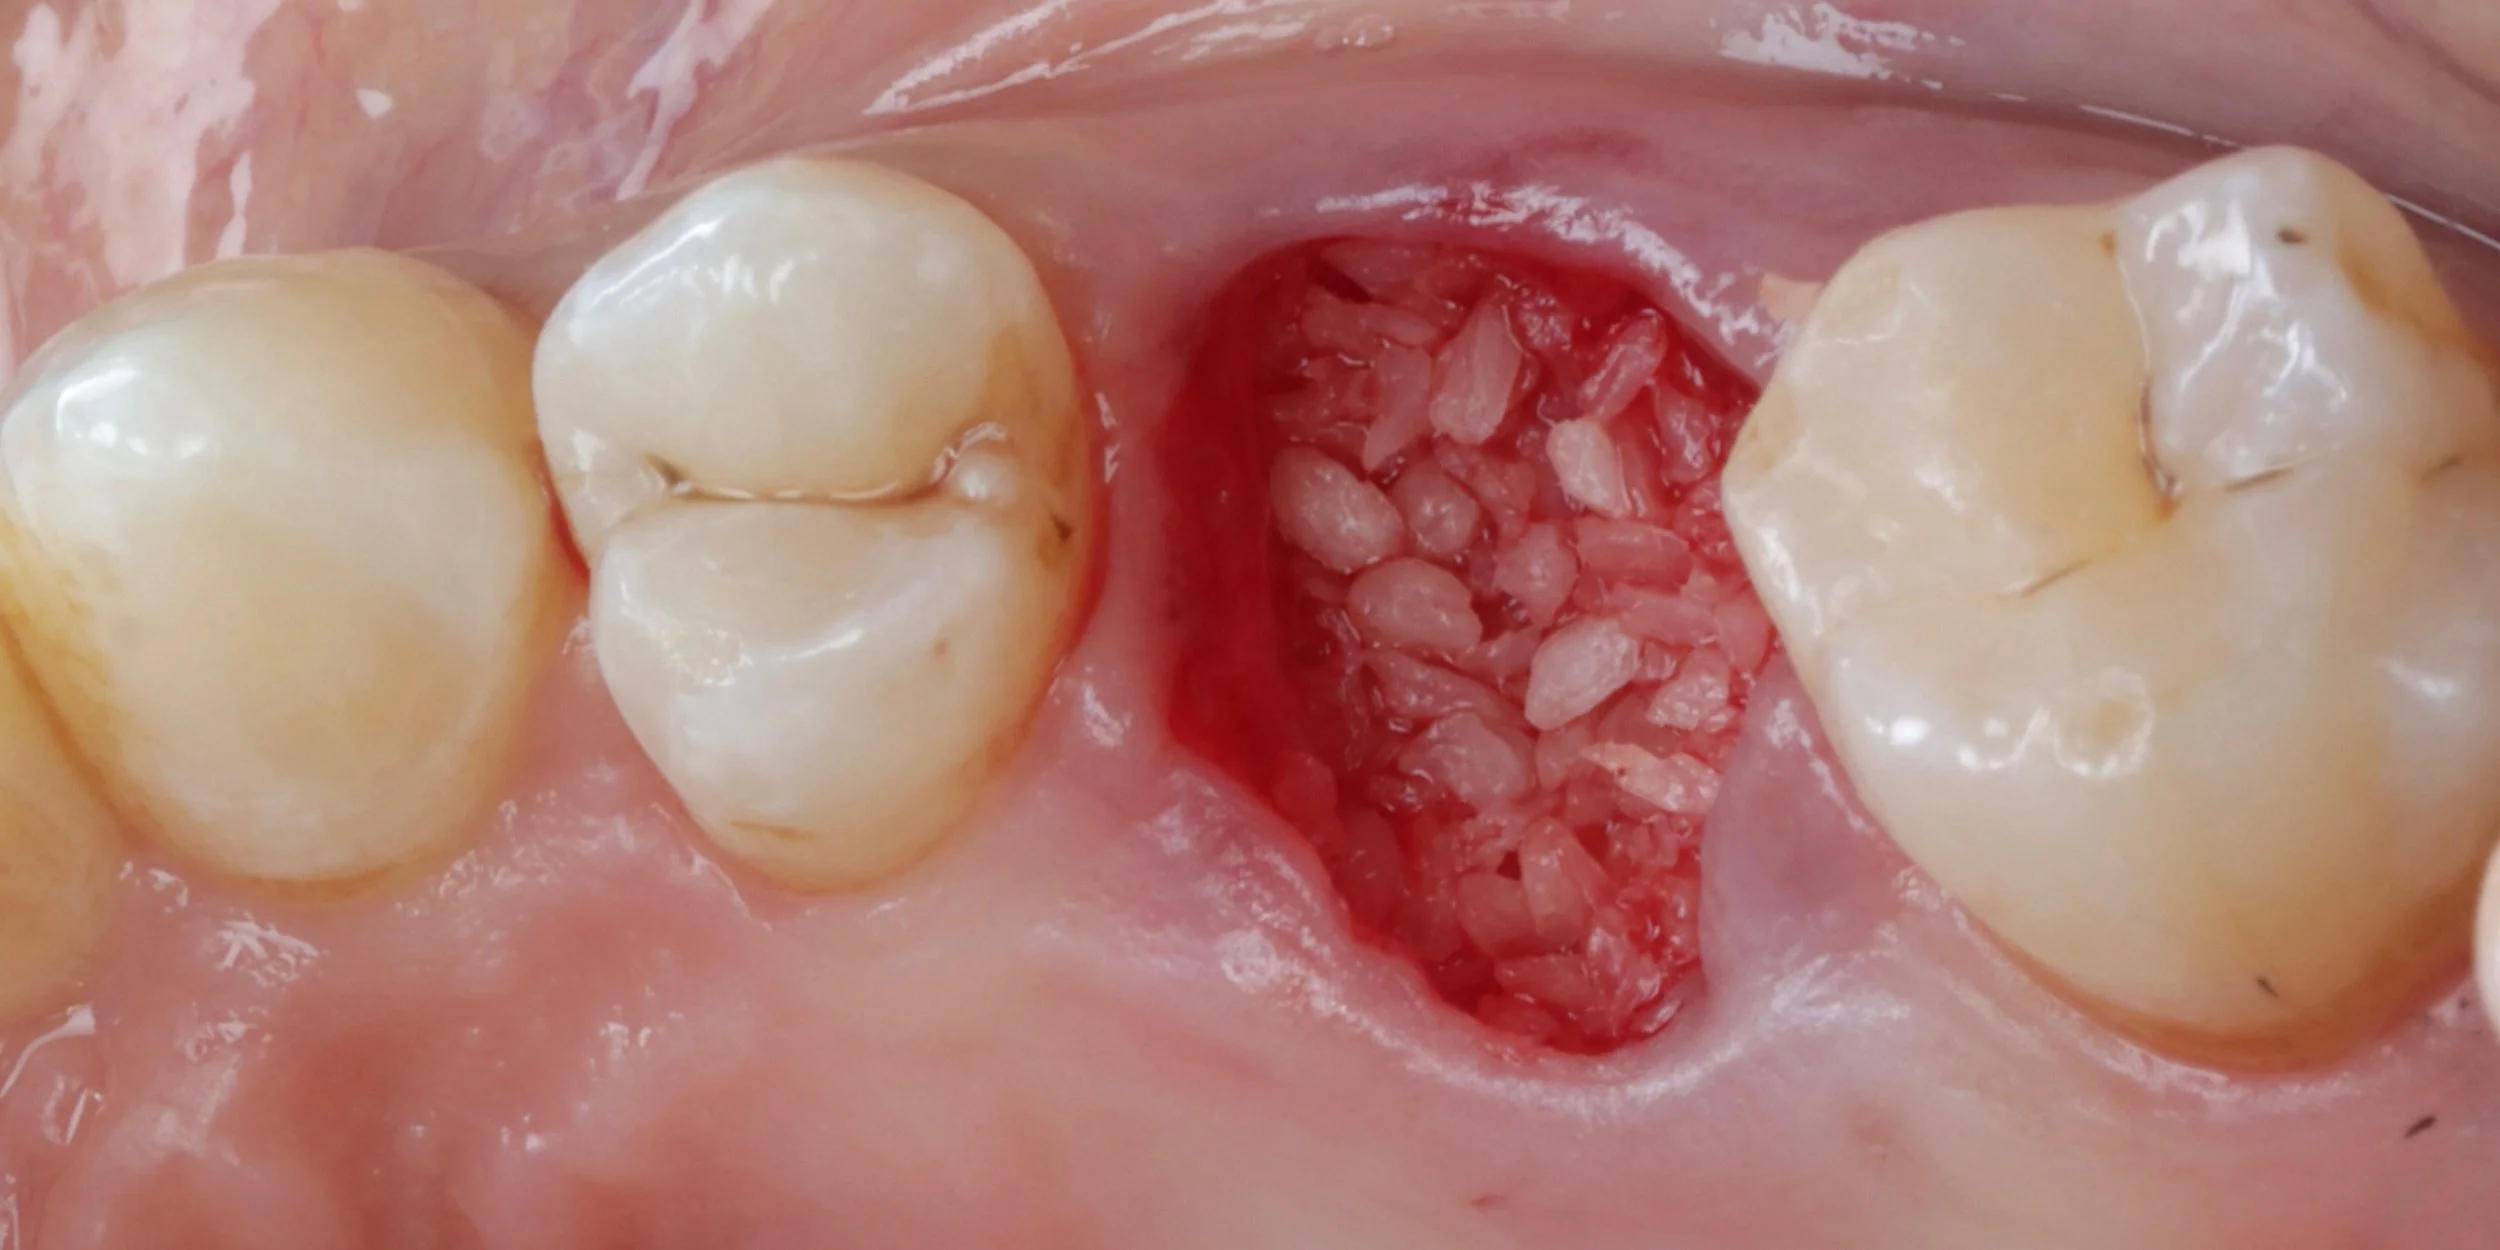

Replace is the 2 day immediate implant & CTG course you have been waiting for! Replace and recreate nature with immediate implant placement and connective tissue grafting. Learn the secrets of invisible tooth replacement, starting with atraumatic extraction and immediate implant placement. Master the art of connective tissue grafting and emergence profile sculpting using custom provisionals.